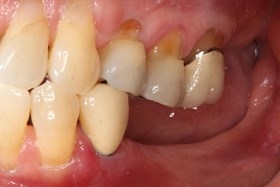

術前缺牙無法咀嚼